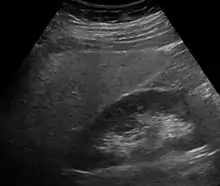

Ultrasound showing diffuse increased echogenicity of the liver.

Imaging studies are often obtained during the evaluation process. Ultrasonography reveals a "bright" liver with increased echogenicity. Medical imaging can aid in diagnosis of fatty liver; fatty livers have lower density than spleens on computed tomography (CT), and fat appears bright in T1-weighted magnetic resonance images (MRIs). Magnetic resonance elastography, a variant of magnetic resonance imaging, is investigated as a non-invasive method to diagnose fibrosis progression.[28] Histological diagnosis by liver biopsy is the most accurate measure of fibrosis and liver fat progression as of 2018.[6]